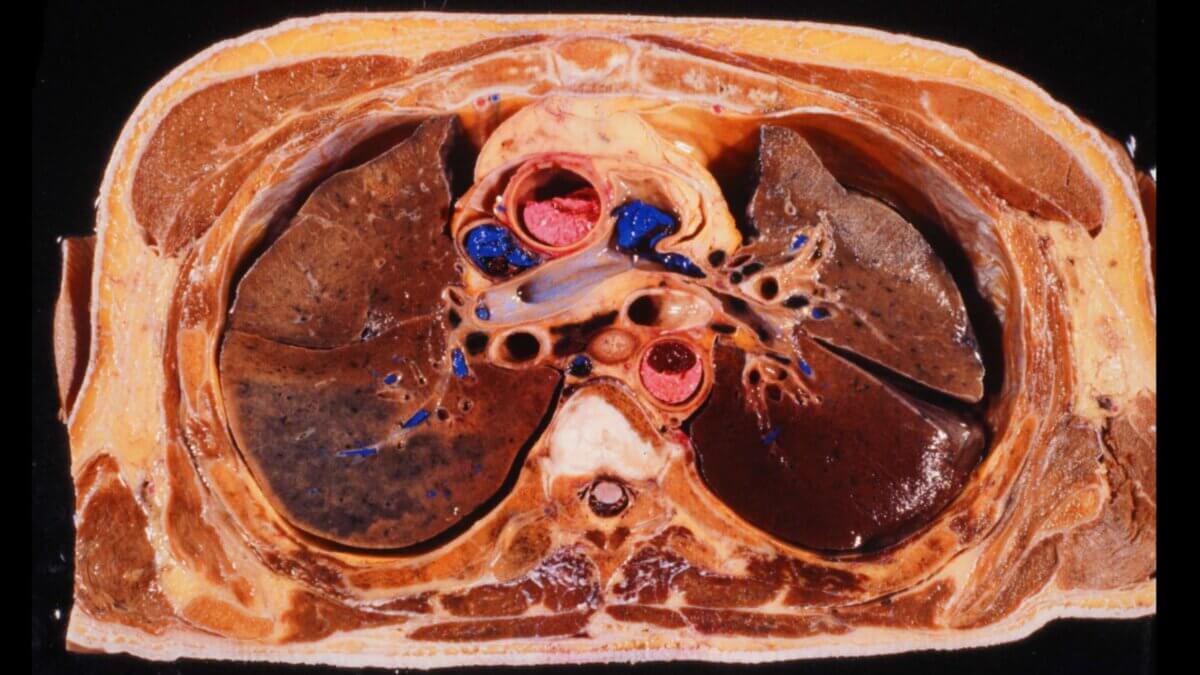

Präparat

- Präparat freundlicherweise zur Verfügung gestellt durch die Anatomie der Uni Köln